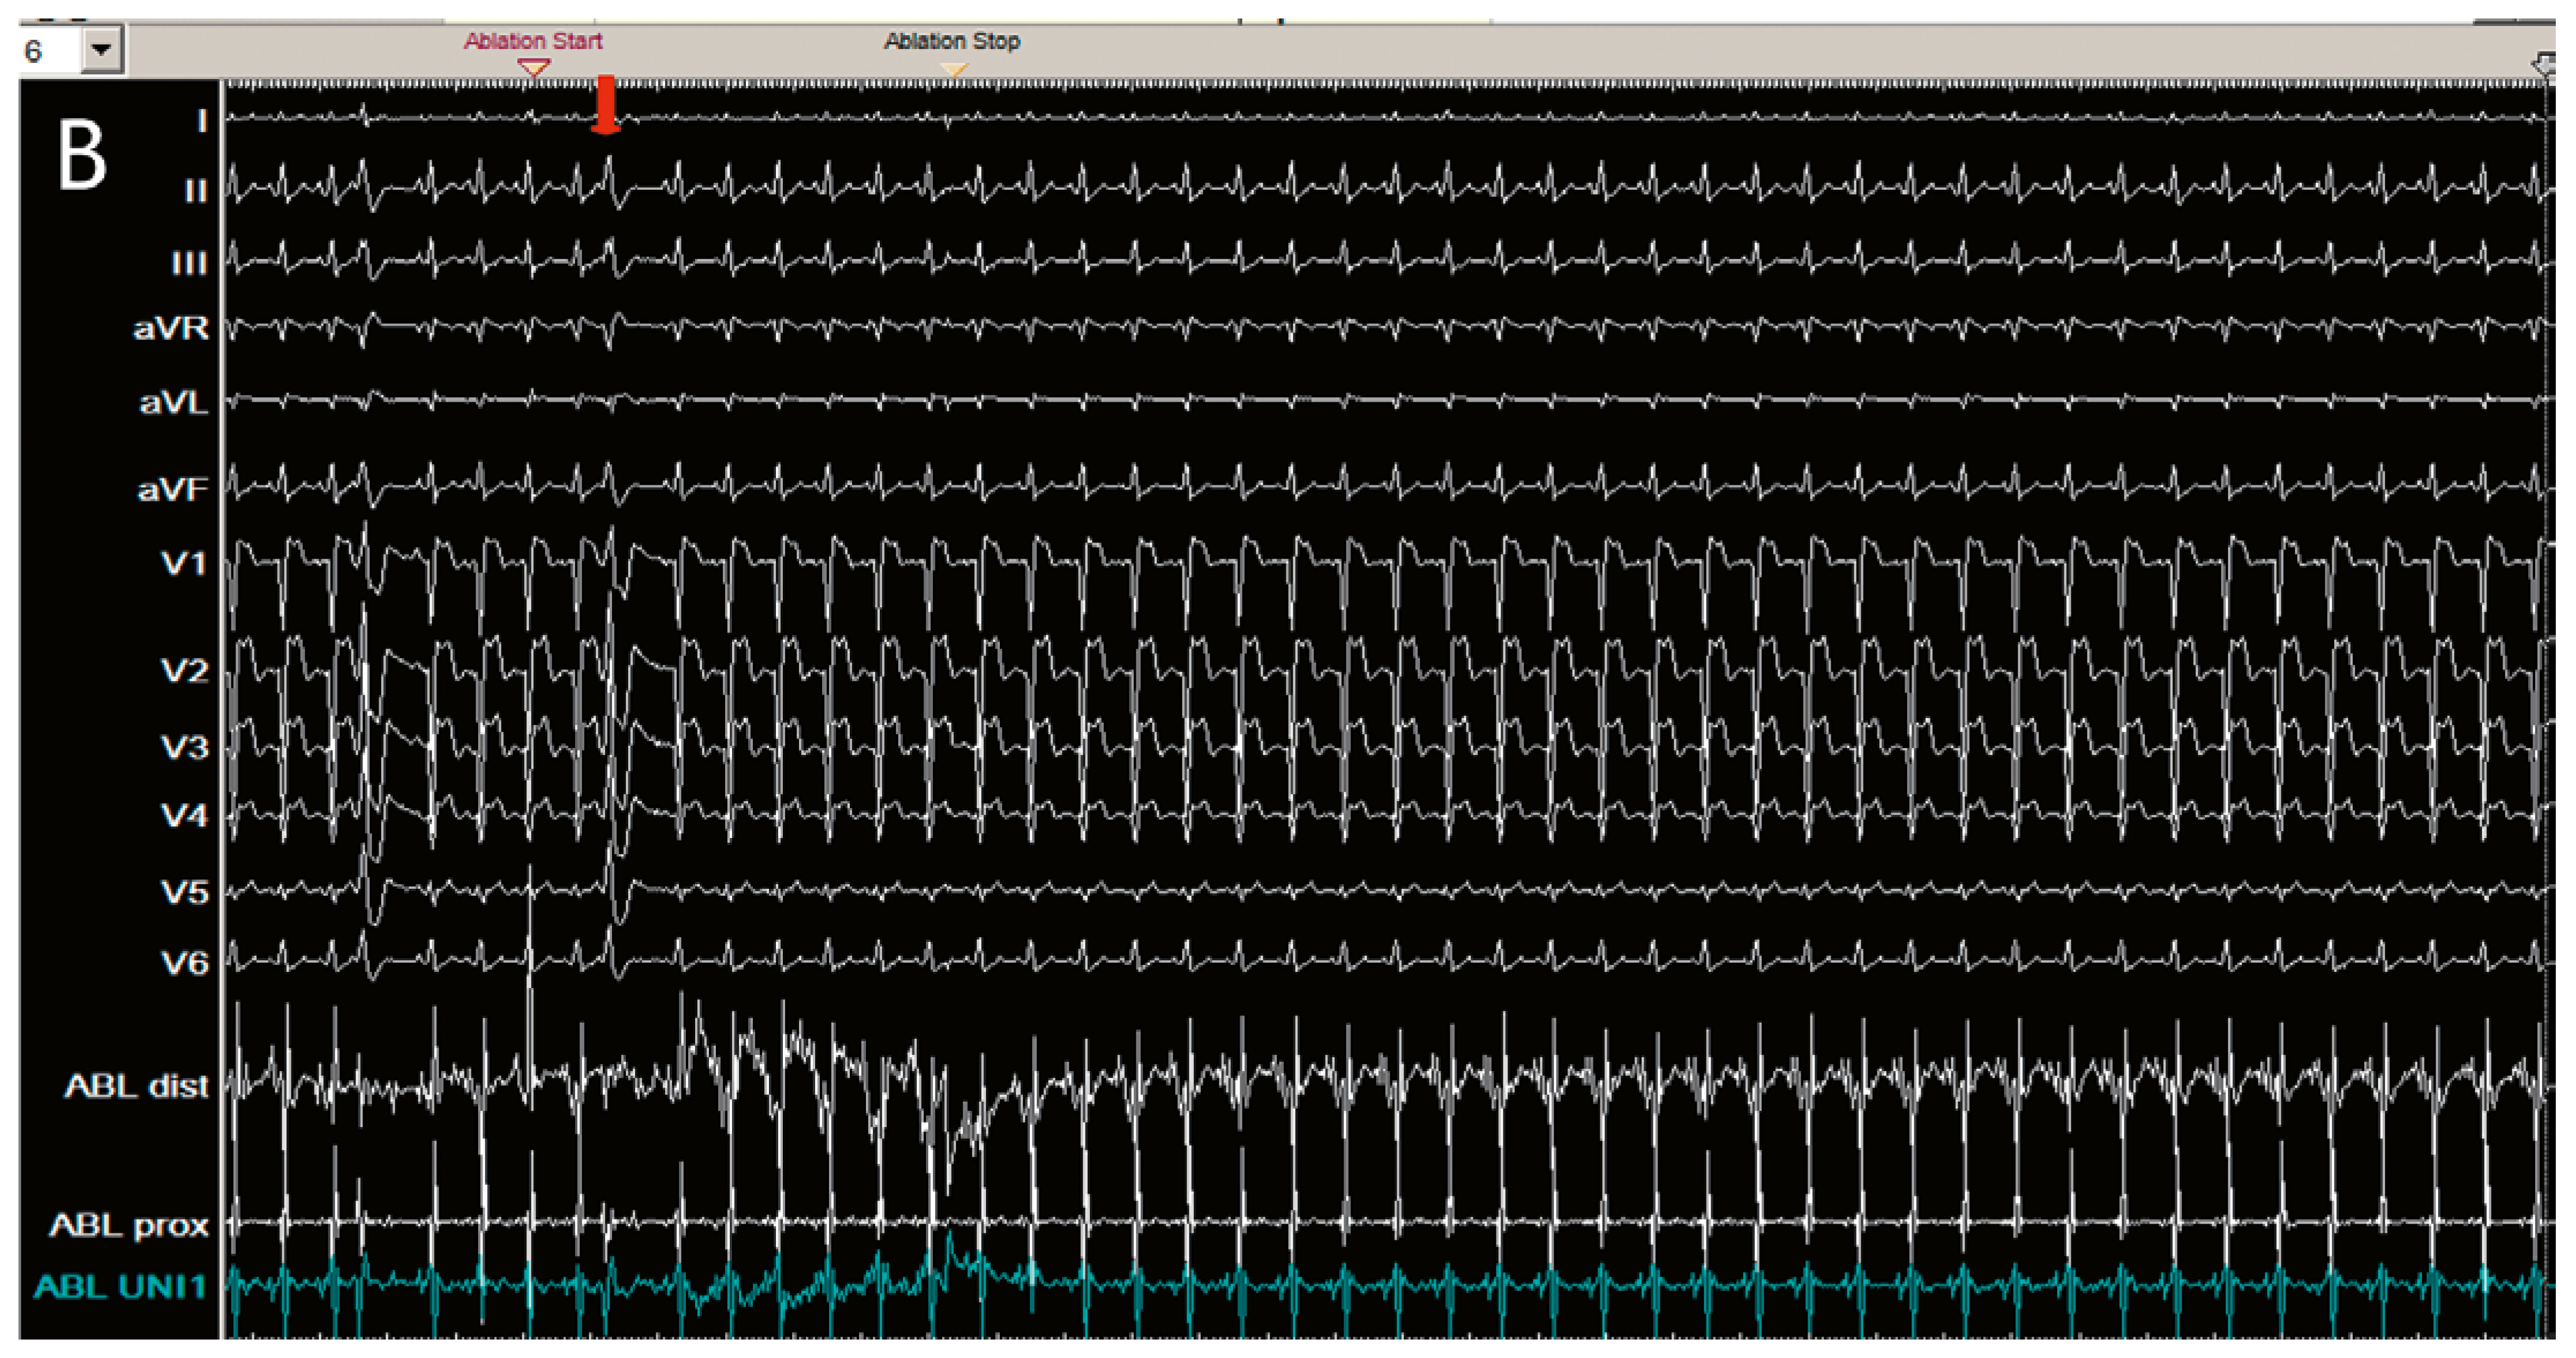

Clinical case